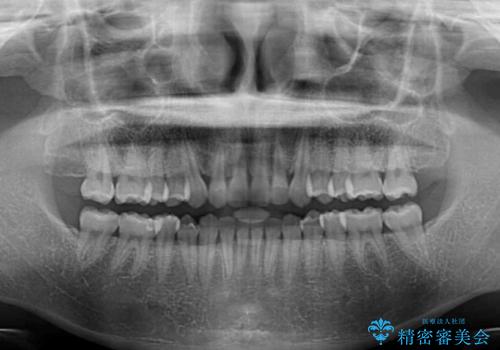

【モニター】前歯の歯列不正をワイヤー装置で短期間矯正治療

- 前歯の隙間やクロスバイトを気にして来院された患者様です。

結婚式の予定があり、可能であれば結婚式までに治療を終えたいとのことで、短期間で治療をおける可能性の高いワイヤー装置にて矯正治療を行うこととしました。

ギリギリとなりましたが、結婚式直前にワイヤー装置を外すことができました。

ワイヤー装置除去後に細かい部分を短期間のマウスピース矯正にて仕上げました。